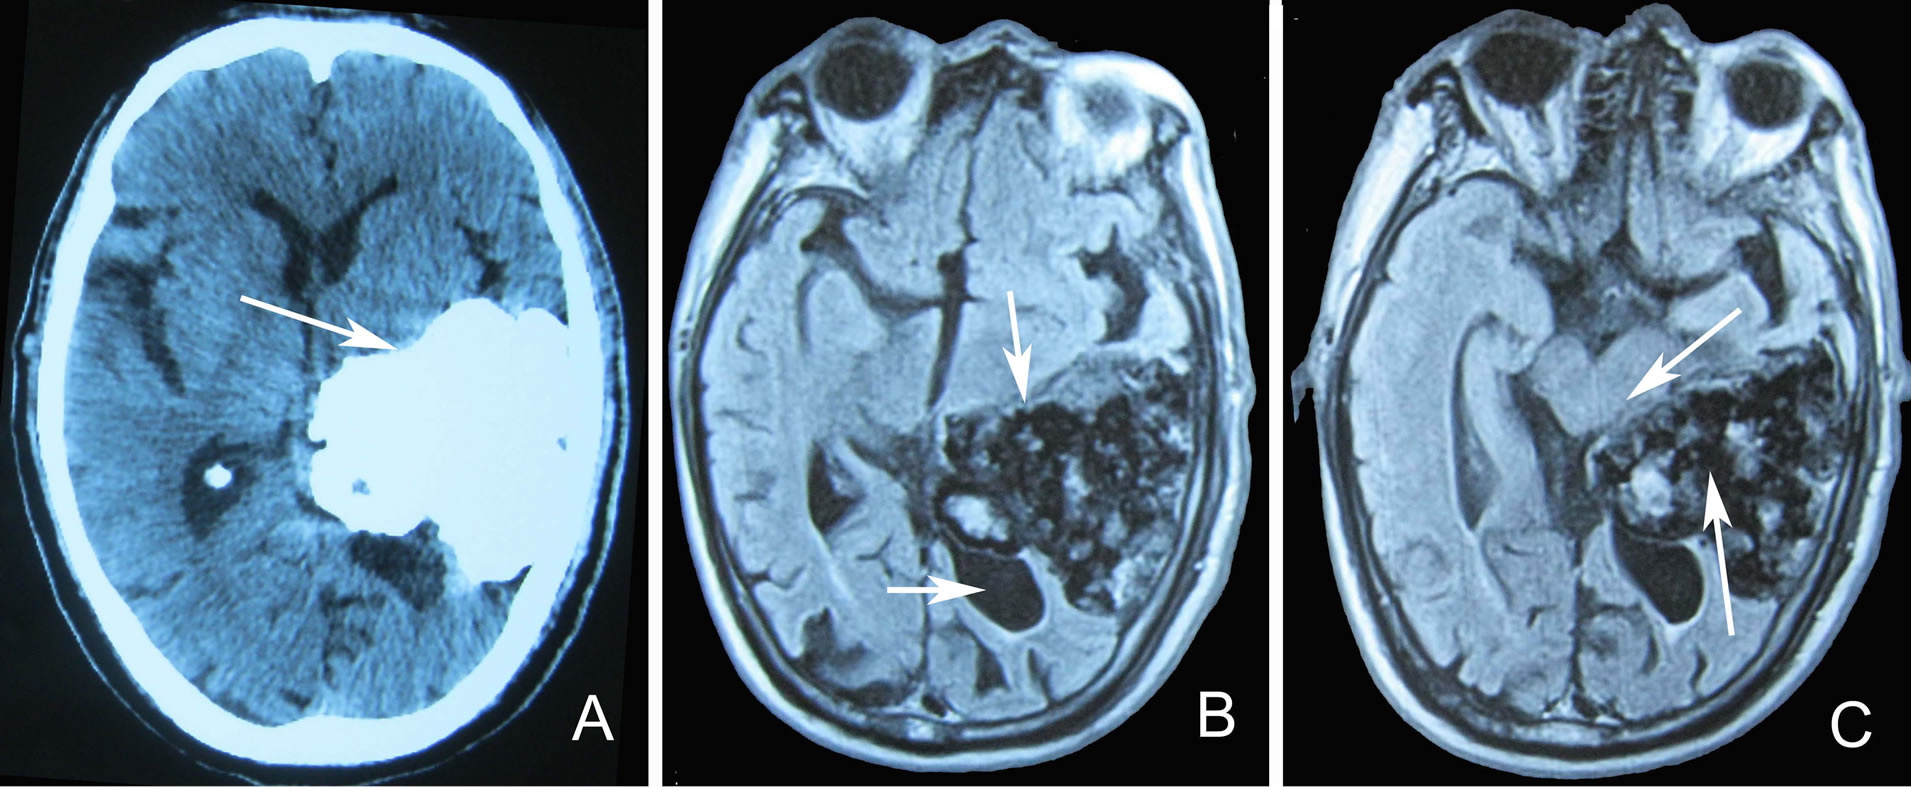

On non-contrast enhanced cranial CT scan, the giant massive of irregular high density (6 × 5 × 6 cm) was found in left temporal lobe region where there was some point flaky low density, and the posterior horn of the left lateral ventricle downward shift (Figure 1A); enhanced CT scan no enhancement. Magnetic resonance imaging (MRI) on brain showed an irregular huge tumor in the left temporal lobe area, the midline shift to the right, the posterior horn of the left ventricle compressed downward shift, expansion, and hydrocephalus (Figure 1B). The huge tumor presented extending to the infratentorial brainstem, and obviously midbrain compressed and displacement, and multiple nodular or lobulated mixd high and low or equal signal, in which the liquid signal based (Figure 1C). Enhanced MRI was without enhancement. The huge congenital intracranial teratoma was diagnosed. On follow-up a year, in addition to occasional headache, He was no other abnormalities and as usual in the daily life and work.

Figure 1. A 77 years old patient with congenital brain teratoma brain imaging. Non-contrast enhanced CT scans show a 6 × 5 × 6 cm huge tumor of irregular high density in the left temporal lobe of the patient (A). MRI show an irregular huge tumor in left temporal lobe area (B. upper arrow), with the midline shift to the right, the posterior horn of the left ventricle compressed downward shift, expansion, and hydrocephalus (B. below arrow), and extending to the infratentorial brainstem, resulting in midbrain compression and displacement (C. upper arrow); on FLAIR show multiple nodular or lobulated mixed high and low or equal signal, in which the liquid signal based (C. below arrow).